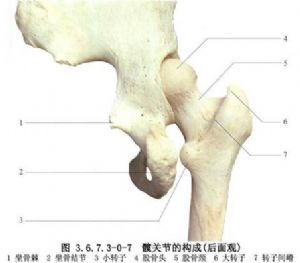

依據髖脫位後股骨頭所處的位置不同,可將髖脫位分爲三類:①髖關節前脫位;脫位後的股骨頭停留在髂、坐骨結節連線前方者。②髖關節後脫位:股骨頭脫位後停留在髂、坐骨結節連線後方者。③髖關節中心脫位:股骨頭受暴力向髖臼中心推擠,衝破髖臼底或穿透髖臼底部骨折裂隙而突入盆腔者。三種類型中以髖關節後脫位最爲多見(圖3.6.7.3-0-1~3.6.7.3-0-10)。

手術相關解剖見下圖(圖3.6.7.3-1~3.6.7.3-4)。